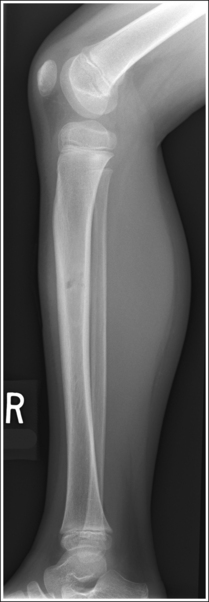

Image density is uniform across the lower leg.

• Position the thicker proximal lower leg at the cathode end of the tube and the thinner distal lower leg at the anode end to take advantage of the anode heel effect and obtain more uniform density across the lower leg.

The lower leg demonstrates an AP projection. The tibia demonstrates only minimal superimposition of the proximal and distal fibula, and the fibular midshaft is demonstrated free of tibial superimposition.

• To obtain an AP projection of the lower leg, place the patient in a supine position with the knee fully extended and the foot placed vertically. Dorsiflex the foot to a 90-degree angle with the lower leg (Figure 6-65).

• Detecting lower leg rotation. Rotation of the lower leg can be identified on an AP lower leg projection by evaluating the relationship of the fibula to the tibia. When the patient's leg is externally (laterally) rotated, the fibula shifts toward and eventually beneath the tibia, obscuring the medial mortise (see Image 48). When the patient's leg is internally (medially) rotated, the head of the fibula draws from beneath the tibia (see Image 49).

The knee and tibiotalar joint spaces are closed.

• The proximal tibia slopes distally from the anterior condylar margin to the posterior condylar margin by approximately 5 degrees. When the lower leg is placed parallel with the IR and the central ray is centered to the midshaft of the lower leg, x-rays that diverge in the opposite direction are used to record the image of the proximal tibia (see Figure 6-66). The distal lower leg also slopes distally from the anterior tibial margin to the posterior margin by approximately 3 degrees. Although the x-rays diverge in the same direction as the slope of the distal tibia, they diverge at a greater angle. Because the angle of x-ray divergence is not aligned parallel with either the proximal or distal tibia, the knee and ankle joints are demonstrated as closed spaces on an AP lower leg projection.

The tibial midshaft is at the center of the exposure field. The tibia, fibula, ankle, knee, and surrounding lower leg soft tissue are included within the collimated field.

• A perpendicular central ray is centered to the midpoint of the lower leg to place it in the center of the image.

• To include the ankle and knee joints on the image, you must consider the degree of x-ray beam divergence that occurs when a long body part is imaged (Figure 6-66). A 14- × 17-inch (35- × 43-cm) detailed screen-film or computed radiography IR should be adequate to include both the ankle and knee. When a screen-film system is used, the leg can be positioned diagonally to accommodate the length. For the computed radiography system, it is not advisable to do this unless the system is set to handle this alignment. To ensure that both joints are included, the film should extend 1 to 1.5 inches (2.5 to 4 cm) beyond each joint space. The ankle is located at the level of the medial malleolus, and the knee joint is located 1 inch (2.5 cm) distal to the palpable medial epicondyle.

• Once the lower leg is accurately positioned with the IR, center the central ray to the midpoint of the lower leg and open the longitudinal collimation field until it extends just beyond both the knee and the ankle. For patients with long lower legs, it may be necessary to raise the source–image receptor distance (SID) above the standard to obtain a longitudinally collimated field long enough to include both joints on the same IR. Transverse collimation should be to within 0.5 inch (1.25 cm) of the lower leg skin line.